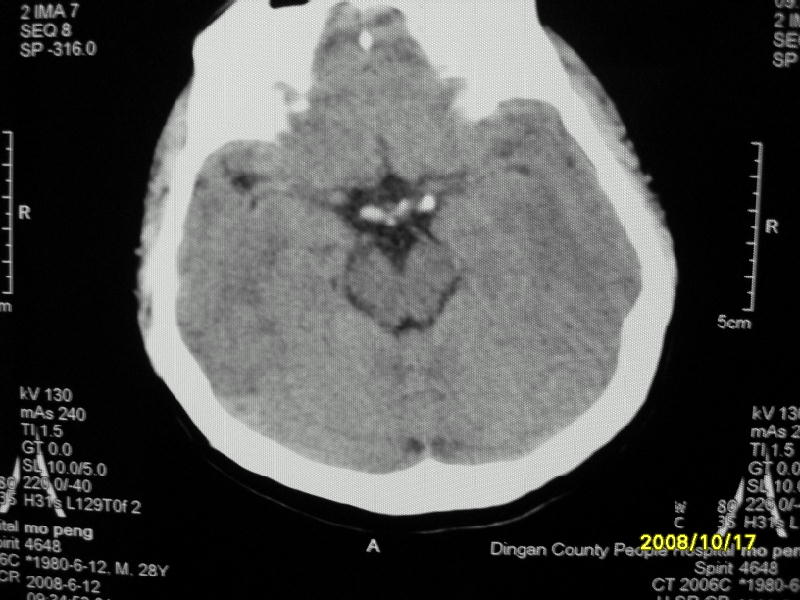

检查名称:     ct颅脑平扫           男     28岁

表现:左顶叶见斑点状致密影。边缘清,大小约0。3*1。0cm,余脑实质密度及灰白质结构示见异常。脑室系统大小,形态,密度未见异常。脑沟。脑裂。脑池未见异常密度影。中线结构无移位。

印象:左顶叶少许钙化灶

左顶叶见斑点状致密影。边缘清,大小约0。3*1。0cm,余脑实质密度及灰白质结构示见异常。脑室系统大小,形态,密度未见异常。脑沟。脑裂。脑池未见异常密度影。中线结构无移位。

印象:左顶叶少许钙化灶。

考虑脑膜钙化或脑膜血管钙化

镰旁钙化或顶骨内板骨嵴部分容积效应,建议mri矢状位扫描观察与顶骨的关系。排外后者。